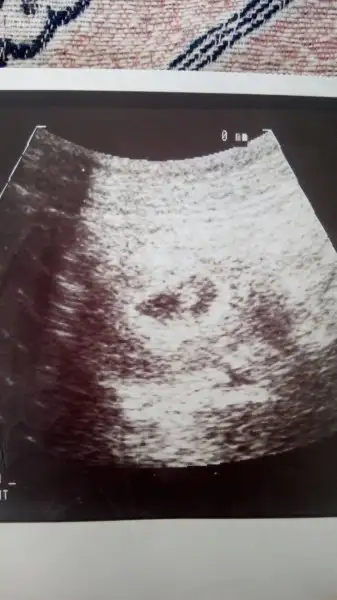

Canim karindan ultrasyon sanirim burdaki teoriye gore kiz. Ama burdaki teori venimkinde tutmadi bende 6 haziranda dogum yaptim ve bebegim oglandi. Seninki benimkine cok benziyor

Canim kizinin varsa böyle ilk ultrason fotolari yükle ozaman daha net ortaya cikiyo cünkü her kadin genelleme kizi bi tarafta erkegi bi tarafta tasiyo sag sol o kadina göre deisiyp bendede tutmadi teori :)